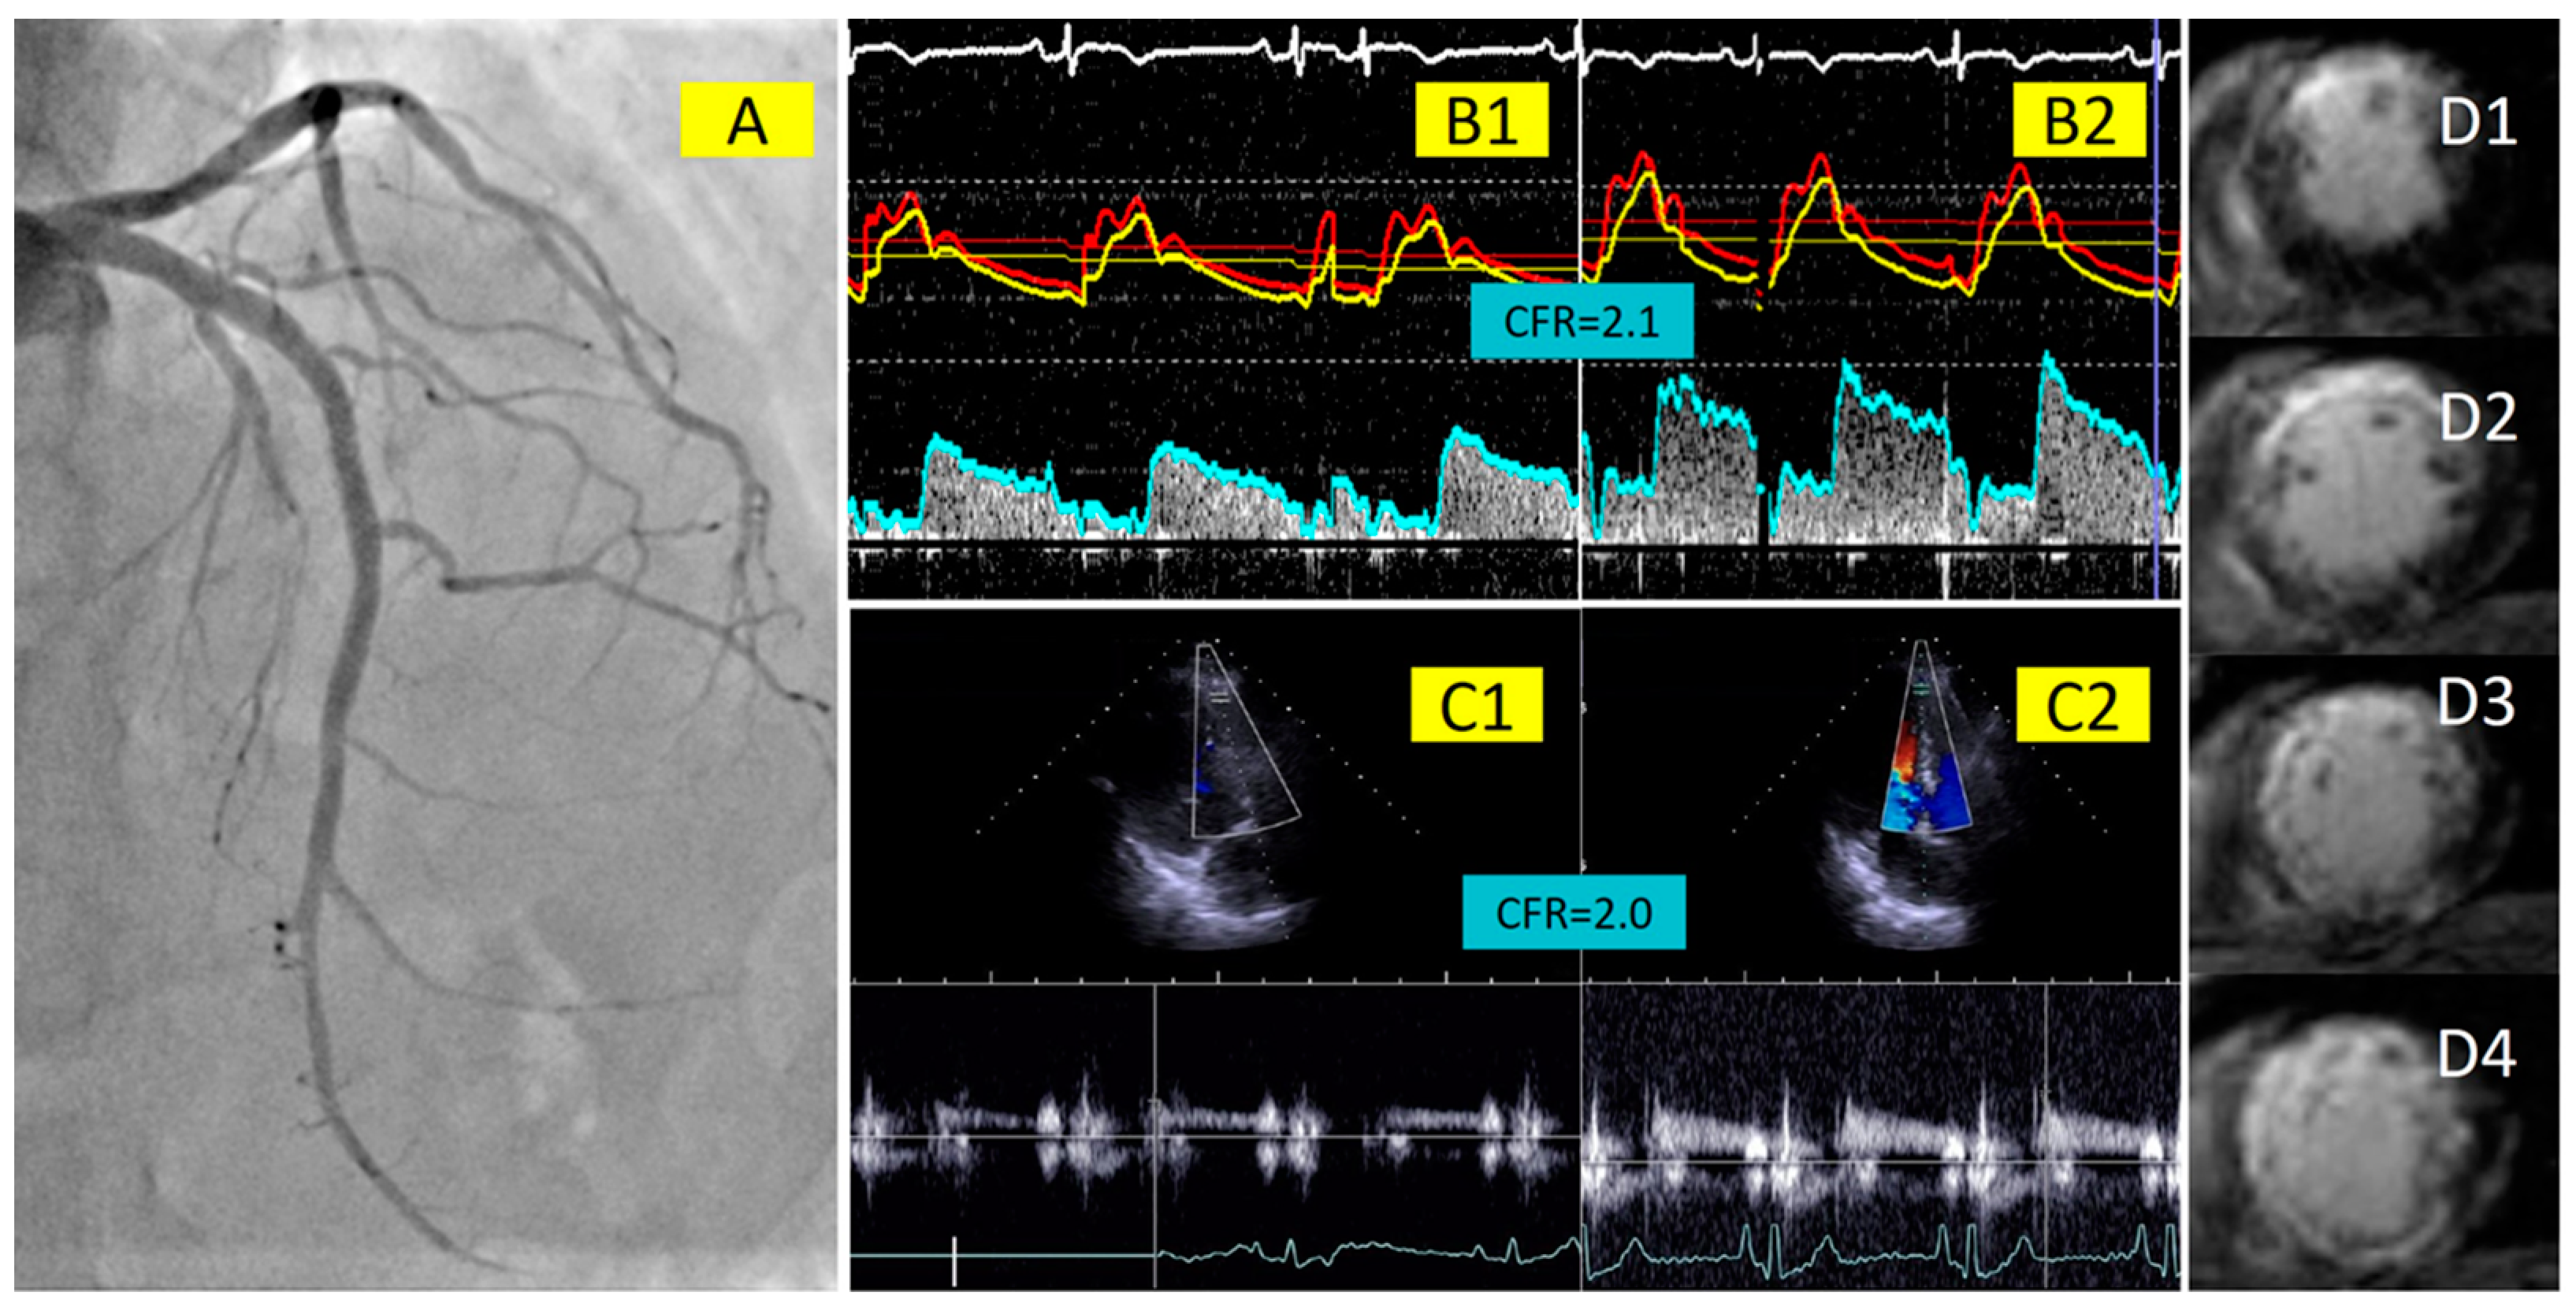

3.2. Correlation between Invasive and Non-Invasive CFR

3.3. Association of Invasive and Non-Invasive CFR with Final Infarct Size